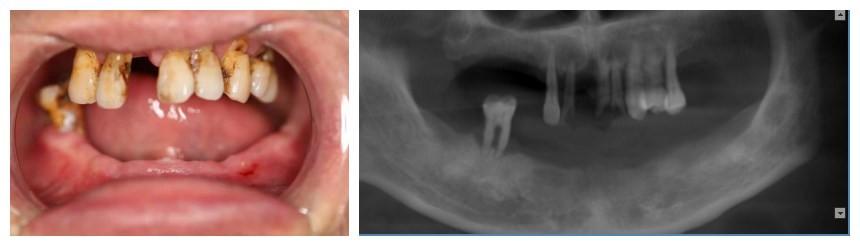

錢主任給予王先生口腔檢查,發(fā)現(xiàn)他有嚴重的牙周病,下頜牙基本全部脫落,上頜后牙也全部脫落只剩下幾顆松動的前牙,根本無法咀嚼食物。給予口腔CT檢查后,錢主任發(fā)現(xiàn),王先生由于長期缺牙,牙槽骨已經(jīng)嚴重吸收,骨條件不理想,但鑒于王先生迫切的希望能盡快恢復(fù)美觀及咀嚼功能,經(jīng)過充分溝通及反復(fù)討論與完善調(diào)節(jié)計劃,終決定給予王先生一次性拔除全部松動牙后行全口種植修復(fù)的方法,讓王先生在當(dāng)天種植術(shù)后當(dāng)天就能擁有一口整齊、漂亮的牙齒。

術(shù)前片